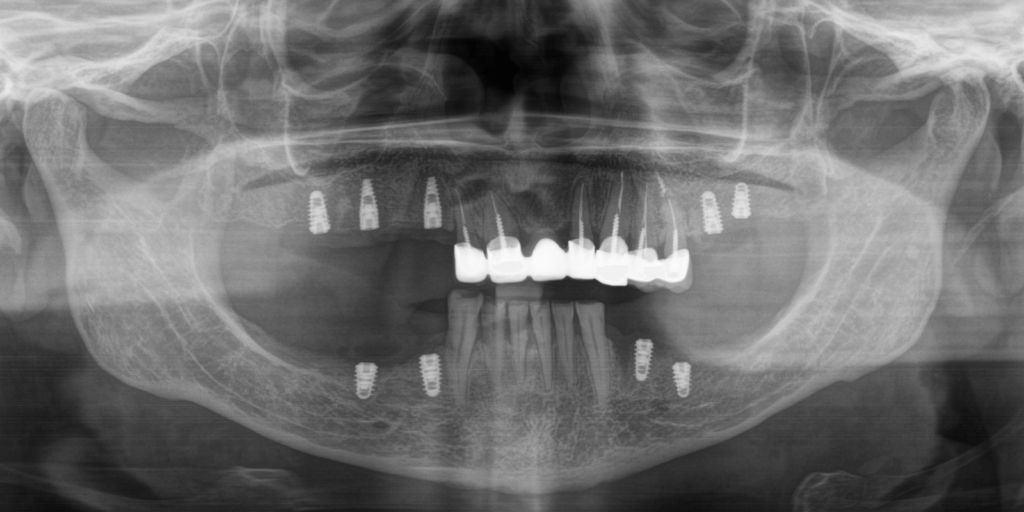

В нашу клинику обратилась пациентка с жалобами на эстетический дефект зубов, и невозможность пережевывать пищу. Врач провел предварительный осмотр и назначил КТ. На полученном КТ-снимке наблюдался металлокерамический мостовидный протез на верхней челюсти, керамическое покрытие на мостовидном протезе было повреждено (со сколами) в результате естественного износа из-за длительной эксплуатации.

- Установить 9 зубных имплантов: 5 – на верхней челюсти и 4 – на нижней.

- Имплантацию зубов выполнить двухэтапной техникой.